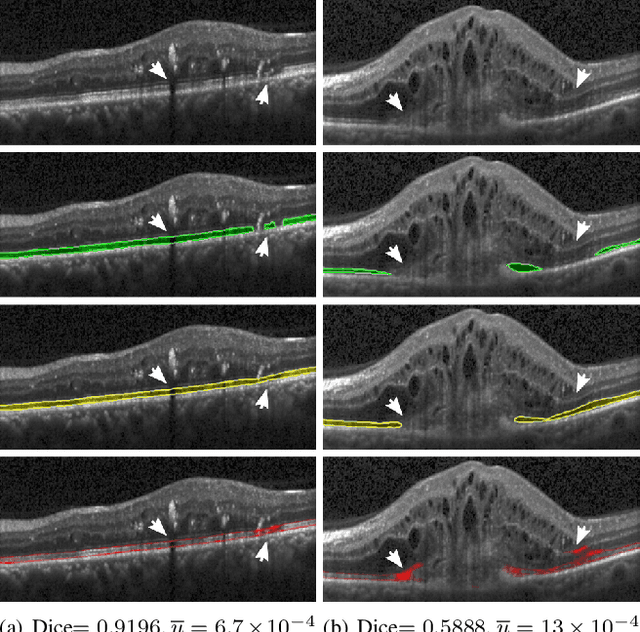

Abstract:In this paper, we introduce a Bayesian deep learning based model for segmenting the photoreceptor layer in pathological OCT scans. Our architecture provides accurate segmentations of the photoreceptor layer and produces pixel-wise epistemic uncertainty maps that highlight potential areas of pathologies or segmentation errors. We empirically evaluated this approach in two sets of pathological OCT scans of patients with age-related macular degeneration, retinal vein oclussion and diabetic macular edema, improving the performance of the baseline U-Net both in terms of the Dice index and the area under the precision/recall curve. We also observed that the uncertainty estimates were inversely correlated with the model performance, underlying its utility for highlighting areas where manual inspection/correction might be needed.